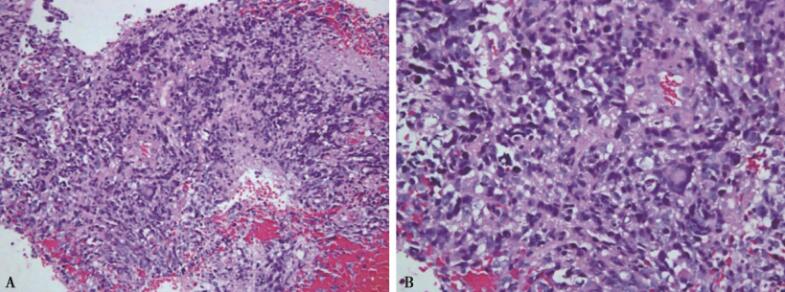

1.病理切片(图3)由病理科送香港中文大学医学院威尔士亲王医院病理解剖及细胞学系主任吴浩强教授共同会诊,会诊意见(2014-9)为间变性星形细胞瘤WHOⅢ级。

图3病理切片

A.瘤细胞弥漫分布,密集成片;血丰富。B.瘤细胞核浆比例高,核异型性明显,部分区域可见菊心团样排列